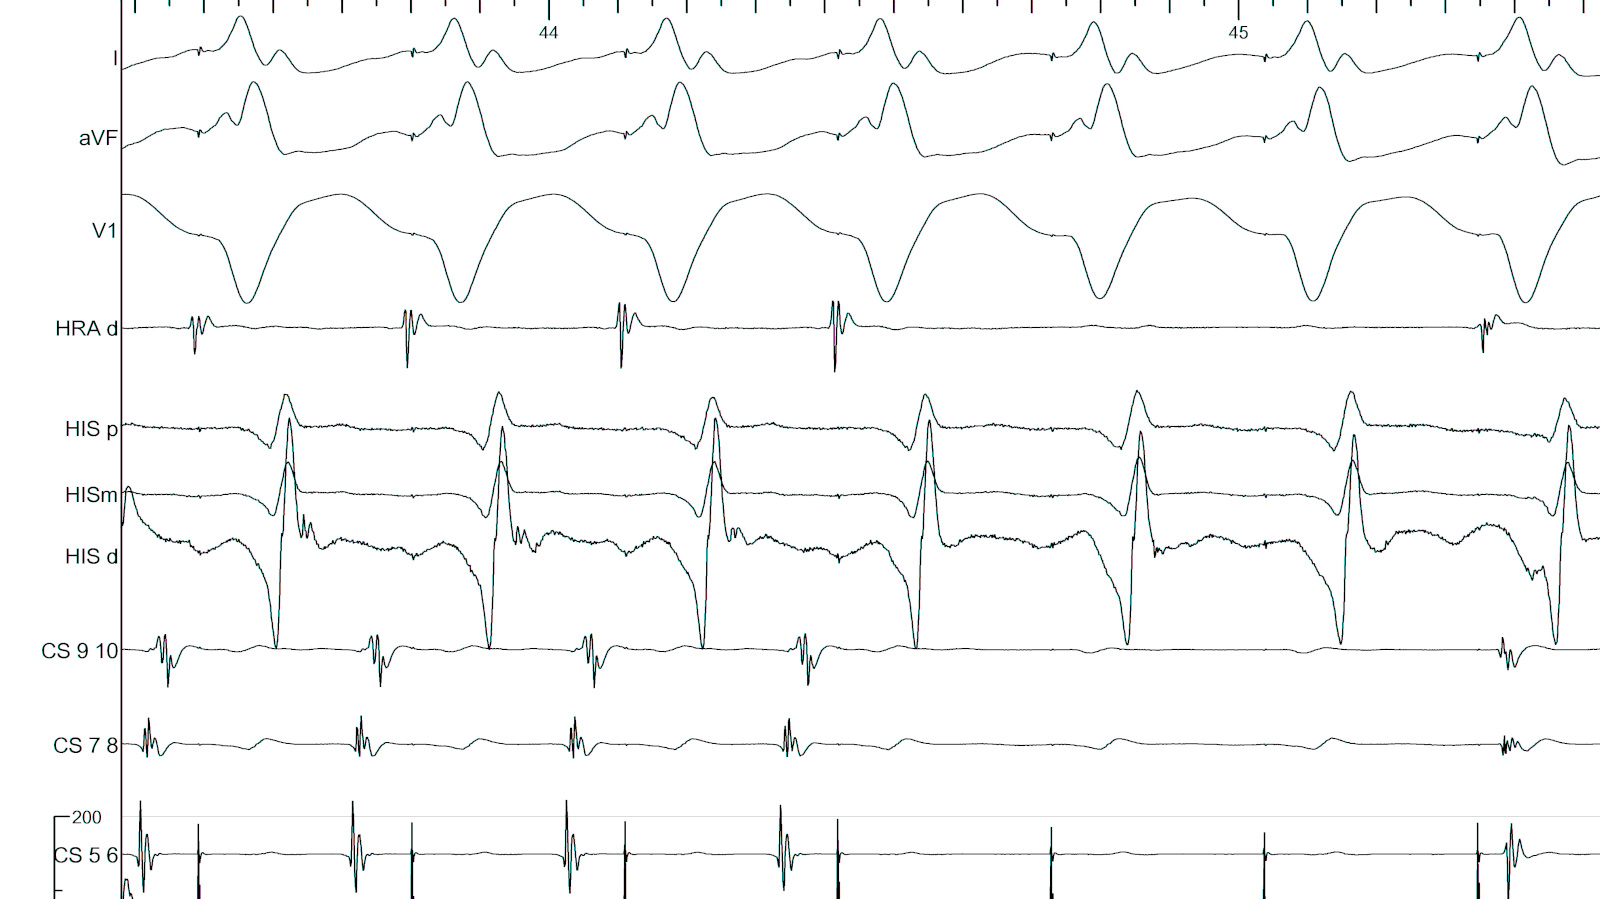

Atrial S1S2 - 600/290 ms

05_ra_600_290.jpg

Parahisian pacing

06_parahisian.jpg